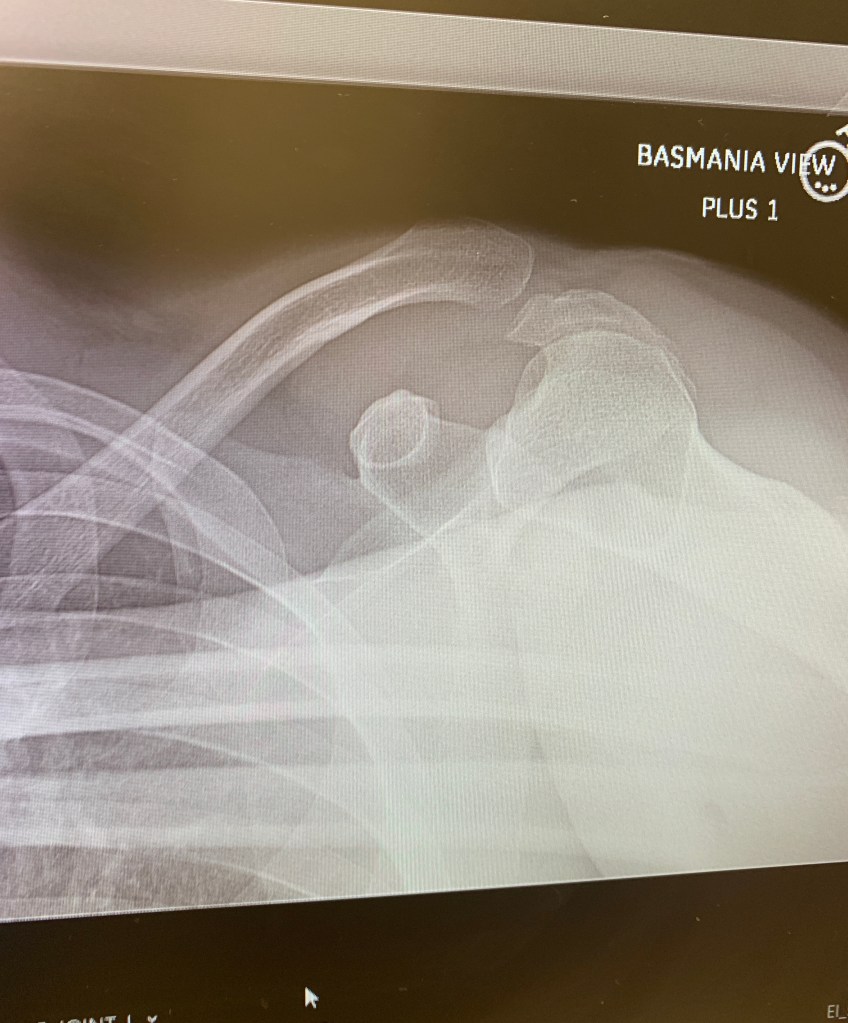

Our old man editor finally gets his wayward clavicle put back into place today at the Hospital For Special Surgery. Frankly, we'll be glad when this is all over. For the last five days since his "cat"-astrophic crash, all his emails, and half of his published stories, have been filled with the most bizarre typos, mostly because he is dictating everything on his iPhone — and Siri doesn't speak Grizzled Tabloidese (admittedly, a dying language).

The doctors gave him 100 percent chance of making a full recovery, which, for Kuntzman, means he'll be back at 75 percent in no time.